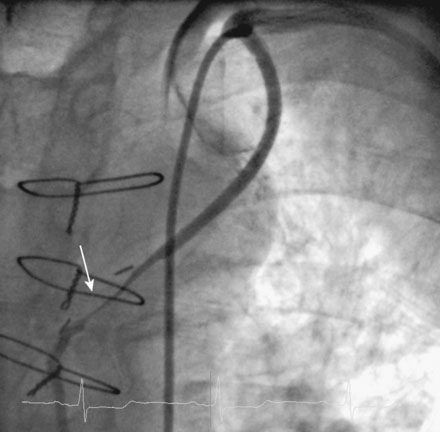

Numerous bare-metal stents were deployed within the left internal mammary artery graft, ultimately requiring a total length of 118 mm to cover the entire dissected area (Figure 33-6 and Videos 33-4, 33-5). Once the operator was satisfied with the repair of the left internal mammary artery graft, attention was turned to the subclavian artery. Angiography confirmed a dissection flap, but this remained stable throughout the procedure, did not compromise the origin of the vertebral artery (Figures 33-7, 33-8 and Videos 33-6, 33-7), and did not result in a pressure gradient across the dissected segment. Because the entry site of the intimal flap was opposite the direction of blood flow, it was decided to treat this dissection conservatively and the procedure was halted.